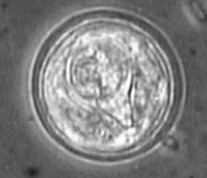

以在宿主糞便中發現孕節或蟲卵而確診。孕節子宮袋狀,蟲卵呈亞球形,直徑為38~45μm,卵殼薄,卵內含一個被帶有雙角的梨樣的殼包裹的六鉤蚴。

司氏伯特絛蟲蟲卵